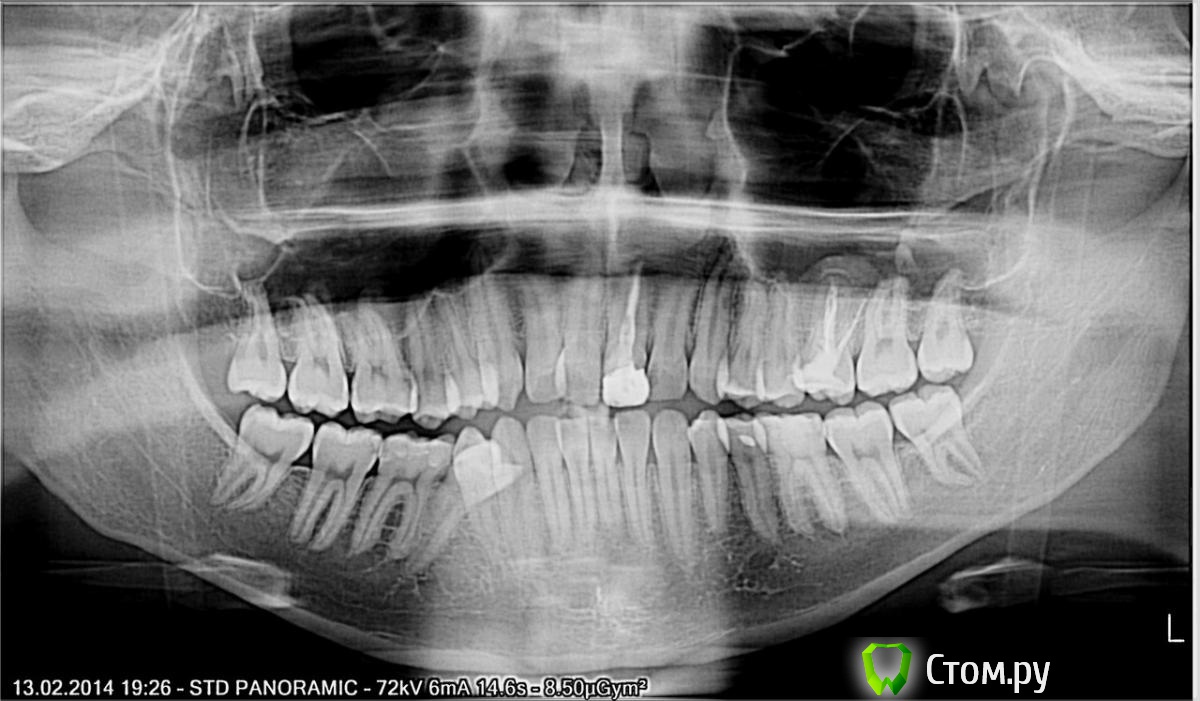

faity Опубликовано 7 июня, 2014 Поделиться Опубликовано 7 июня, 2014 сам не ортодонт, пациент из другой клиники, мой ортодонт пока не смотрел.если не сложно накидайте предварительный план лечения.8-мые дистопированны, 4.5 не в ряду, скученность в переднем отделе, прикус открытый на 0,2-0,5мм, нижние передние выдвинуты мезиальноне судите строго специализация не моя, если есть ещё вопросы- задавайте. Ссылка на комментарий

faity Опубликовано 9 июня, 2014 Автор Поделиться Опубликовано 9 июня, 2014 Модели трг фото во рту и ФАС и профиль. Также клкток, давайте так, я хирургортодонт из другой клиники прислал парня на удаление 4.5, ортодонт поставил дугу на в/ч, от пациента я выяснил что кроме ОПТГ ему ничего не делали, как поставили ему брекеты на верх не знаю, удалять 3.5 доктор не планировал, удалять 4.5 при имеющихся 8-ых я отказался, плюс лишать человека 4.5 с уже имеющимся смешением центра н/ч вправо я не согласен, к тому же без симетричного удаления 3.5, к тому же с имеющимися 8-мыкогда пац дойдет до моего ортодонта и он сделает ему модели, трг, клкт и фото я с удовольствием их приложу, пока же нет ничего кроме оптгмне всего лишь необходимо понять правильно ли я поступил в данной ситуации или нет. Ссылка на комментарий